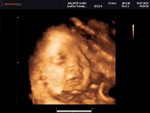

กำลังจะเป็นแม่